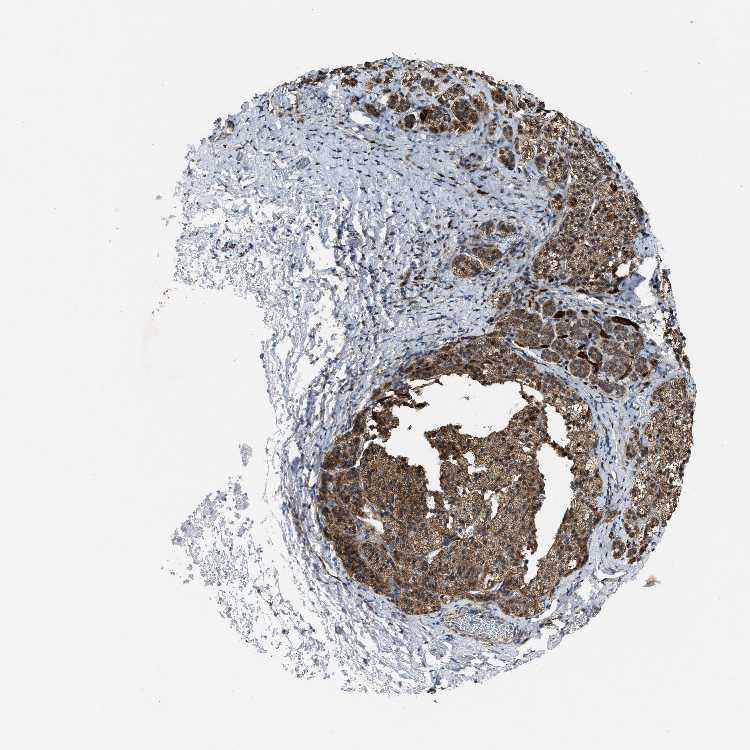

ADRENAL GLAND - Antibody stainingi

Antibody staining in the annotated cell types in the current human tissue is reported as not detected, low, medium, or high, based on conventional immunohistochemistry profiling in selected tissues. This score is based on the combination of the staining intensity and fraction of stained cells.

Each image is clickable and will lead to virtual microscopy that enables deeper exploration of all samples and also displays staining intensity scores, fraction scores and subcellular localization as well as patient and tissue information for each sample.

Antibody HPA021167

Glandular cells High